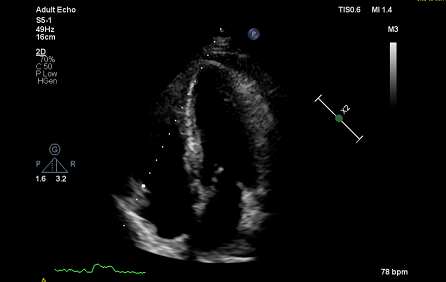

术后超声心动图

患者在院全程积极配合治疗,吉心团队密切协作,以流畅娴熟的技术完成了手术。术后患者状况良好,症状得到改善。